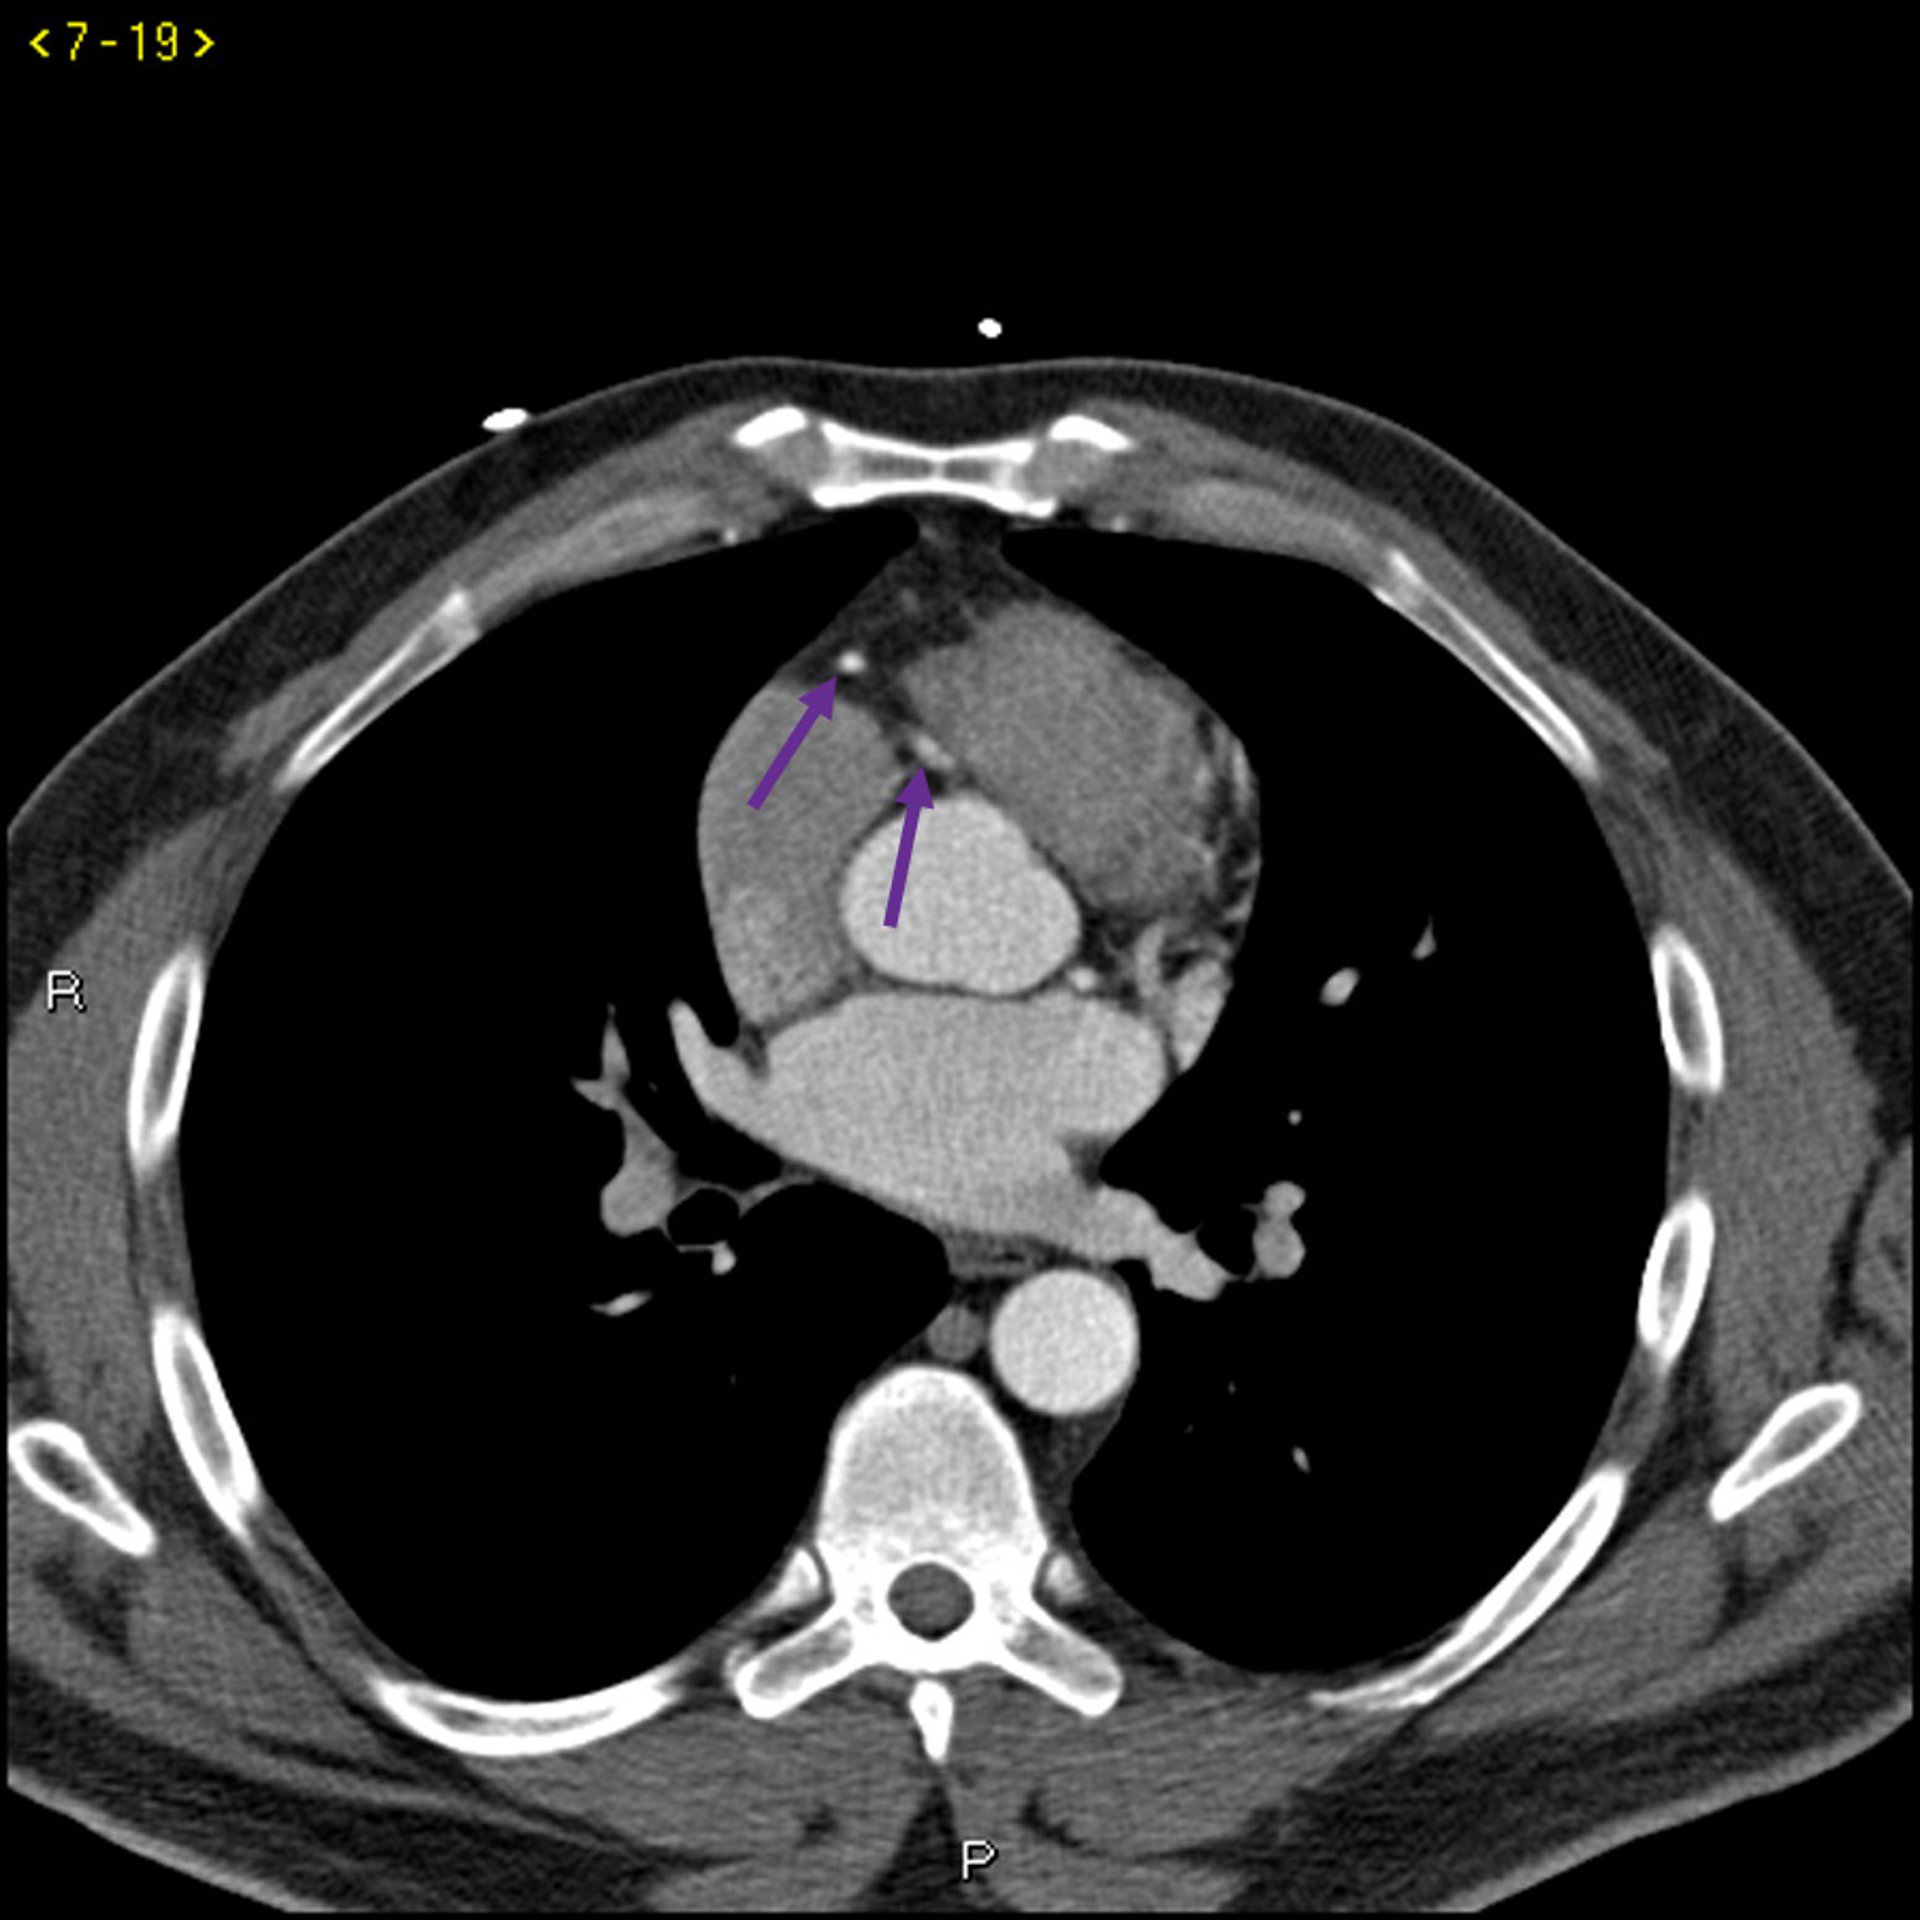

Kontrast CT zeigt normale Koronararterien - Folie 4

Dieses Kontrast-CT zeigt normale Koronararterien. Die linke Hauptleitung ist durch den roten Pfeil gekennzeichnet. Die linke anteriore absteigende Arterie und die linke Zirkumflexarterie sind durch den grünen bzw. blauen Pfeil und die rechte Koronararterie durch den lila Pfeil gekennzeichnet.